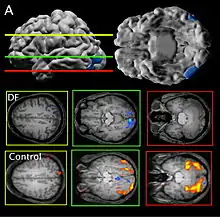

DF Lesion

Patient DF's brain damage resulted from hypoxia due to carbon monoxide poisoning.[2] The lateral occipital cortex (LOC) in her brain is severely damaged and shows no activation presented with line drawings of common objects where healthy people usually do. Moreover, there is a reduction of white matter connections between LOC and other areas.[3] There is also some shrinkage in the intraparietal sulcus, often implicated in the dorsal stream for visuomotor control. The fusiform face area is intact. This would suggest the problem in DF's perception is disconnectivity between higher and lower order functioning.[2]

Recent MRIs have shown many enlarged sulci, like the intraparietal sulcus, parieto-occipital sulcus, and left calcarine sulcus, indicating atrophy.[2] Her visual field remains intact up to 30 degrees.[1]

DF does not benefit from haptic feedback—allowing her to pick up an object does not let her better estimate its width next time.[4] DF also does not use visual information about her grasp: when she can only see her grip in a distorted mirror, her performance does not change.[2] Consistent with all of this, brain imaging has shown no response to line drawings in her ventral stream. Furthermore, according to fMRI studies, the intraparietal sulcus showed preference for grasping motions over reaching motions—actually grabbing an object, in both DF and control patients, activates the intraparietal sulcus more than reaching.[2]